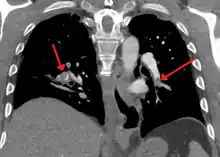

A normal CTPA scan will show the contrast filling the pulmonary vessels, appearing as bright white. Any mass filling defects, such as an embolus, will appear dark in place of the contrast, filling/blocking the space where blood should be flowing into the lungs.

On CTPA, acute emboli have been found at radiodensities ranging between about 5 and 65 Hounsfield units (HU), while chronic emboli have ranged between about 30 and 150.[5]

On CTPA, the pulmonary vessels are filled with contrast, and appear white. Any mass filling defects (embolus or other matter such as fat) appears darker. Ideally, the scan should be complete before the contrast reaches the left side of the heart and the aorta, as this may mean contrast has drained from the pulmonary arteries, or require a larger dose of contrast media.[12]